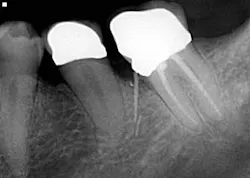

Drill, poke around. Drill some more. Hmm. I’ve got to be getting close. Let’s just take an x-ray to see how close we are . . . oops! Yeah, that’s happened to me and it’s not how I like to start my root canals (figure 1). The cause of perforations during access is primarily due to lack of attention to the degree of axial inclination and failure to hold the bur parallel to the tooth. (1) Inadequate access can also lead to misdirection and unintended gouging. Signs of perforation include sudden pain, hemorrhaging, burning pain or bad taste during irrigation, periodontal ligament reading from the apex locator, and a radiographically malpositioned file. (1) Prevention includes understanding tooth morphology, accessing without a rubber dam (in instances where angulation, calcified chambers, and misoriented crowns skew tooth alignment), (1) having multiple radiographs to reference, and patience . . . lots and lots of patience, especially when you have small, calcified chambers that want to be eluded.

Since I don’t live in my perfect dental world, I enjoy a salt-and-pepper-type of endodontic career. I have an amiable relationship with my referring endodontist, who is there to willingly discuss all things endo, so that my mistakes and mishaps are kept to a minimum. I will confess that he was speechless when I sent him this radiograph to review of a patient who presented for an emergency. Yes, that’s a gutta-percha point with the final crown prepped right on top of it (figure 6). Sometimes, there just isn’t an explanation, and more can be said by saying nothing at all.